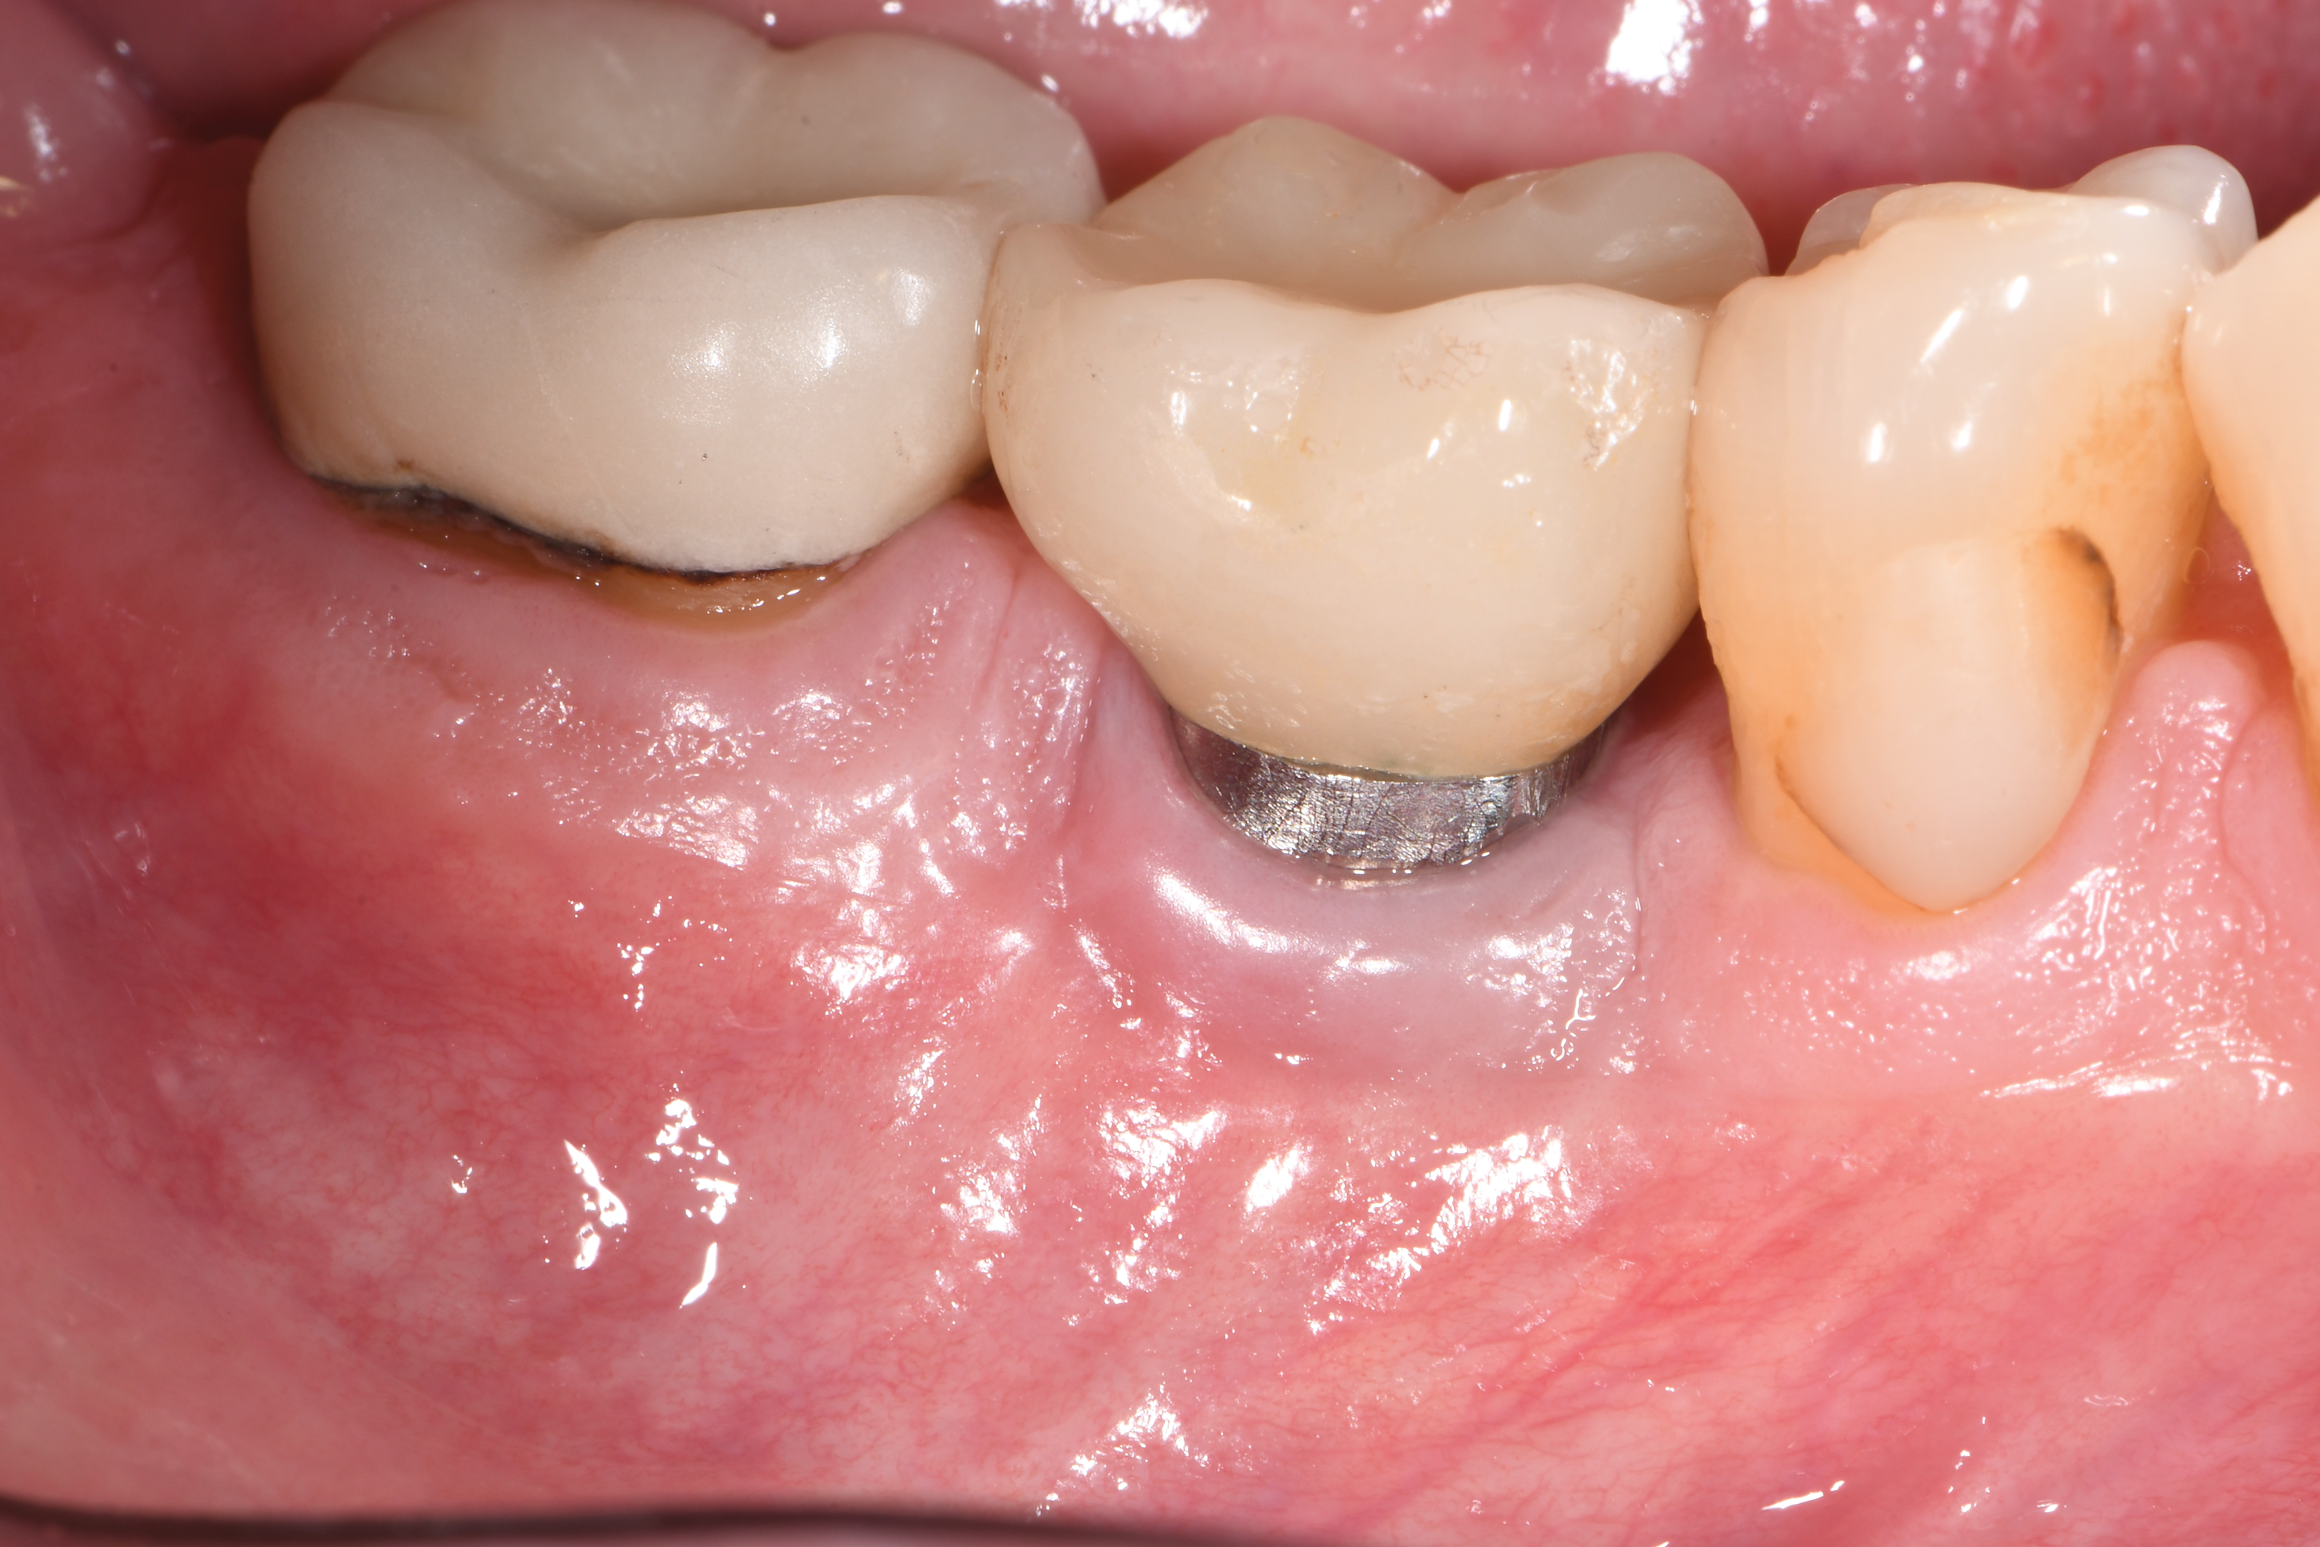

At 10 months (Figure 15), it was decided to modify the phenotype by placing acellular dermal matrix (ADM) to increase the soft-tissue thickness. Upon opening of the site, the osseous fill that had occurred in the mesial infrabony aspect could be visualized (Figure 16), and where there was incomplete thread removal at the distal, this area was slightly modified using the implantoplasty burs. The ADM allograft was placed and secured with 5-0 chromic gut suture using an interrupted technique (Figure 17), and the flaps were secured with 5-0 PTFE. At 15 months post-surgery, probing depths ranged up to 4 mm with the absence of bleeding, and the phenotype had been favorably modified (Figure 18).

Fig 15. Healing at 10 months postoperative. Although now thinner than preoperatively, the gingival tissue appeared healthier.

Figure 15

Fig 16. The site was exposed for placement of an acellular dermal graft to improve the phenotype. Note the hard-tissue fill at the mesial portion of the lesion, which extended to the lingual. One thread next to the bone at the distal was reduced with implantoplasty.

Figure 16

Fig 18. Buccal view at 15 months postoperative. Health was restored to the site with mostly 4 mm probing depths and absence of bleeding. Some interproximal and facial recession of the gingiva had occurred.

Figure 18